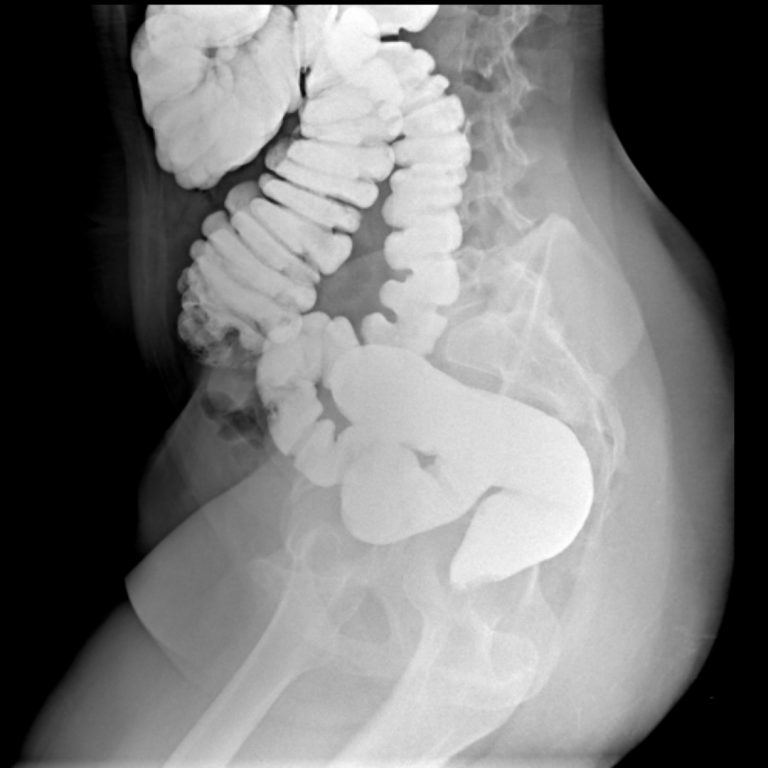

KOLON GRAFİLERİ

İki çeşit baryumlu kolon incelemesi vardır; tek kontrast ve çift kontrast. Kolon kanseri taramasında genellikle çift kontrastlı kolon tetkiki kullanılır.

- Tek Kontrastlı Kolon grafisi

Teknisyen makata bir tüp yerleştirir ve tüpün ucu baryum solüsyonunun olduğu torbaya bağlanır. Verilen baryum yavaşça kolonu sıvar. Bu şekilde kolon görünür hale gelir. Kolon baryum ile doldukça, dışkılama hissi duyulabilir. Baryum vermek için rektuma yerleştirilen tüpün ucunda küçük bir balon vardır. Tüp yerleştirildikten sonra baryum kaçışını engellemek için bu balon şişirilir. Tetkik esnasında masa üzerinde farklı yönlere dönülmesi istenebilir. Böylece verilen baryum tüm kolon segmentlerini doldurur ve kolonun farklı açılardan izlenmesine olanak sağlar. Filmler çekilirken nefesin tutulması istenir.

2- Çift Kontrastlı Kolon grafisi

Bu işlemin tek kontrastlı tetkikten en önemli farkı, kolonun hava ile doldurulmasıdır. Böylece daha kaliteli görüntü elde edilir. Polip gibi daha küçük lezyonlar rahatlıkla seçilebilir. Kolon tetkiki 20-30 dakikada tamamlanmakla birlikte, nadir durumlarda 45 dakikaya kadar çıkabilir. Bu tetkik karında hafif kramplara neden olabilir. Tetkikin bitimi ile şikâyetler sonlanır. Tetkik bitince rektuma yerleştirilen tüp çıkarılır ve kolonun boşaltılması istenir. Tetkiki takip eden birkaç gün dışkı, içeride kalan baryuma bağlı olarak beyaz, gri veya pembe görünümde olabilir. Geride kalan baryum kabızlığa neden olabileceğinden bol miktarda su içilmesi tavsiye olunur.

Rektal yoldan verilen kontrast madde takıntısız çekuma ulaşmış olup ilioçekal bileşke serbesttir. Apendiks vizüalize olmuştur ve normal görünümdedir. Rektum posterior konturu muntazamdır. Presakral mesafe açıktır. Kolon boyunca belirgin haustrasyon artışı mevcuttur. Sigmoid kolon hafif elonge görünümdedir. Kolon lümeninde doluş defekti lehine bulgu saptanmamıştır. Evakuasyon fazında sağ kolon ve hafif sigmoid kolon içinde remnant kontrast madde kalmıştır. Diğer segmentlerdeki kontrast maddenin bulunmaması mukozanın ödemli olabileceğini düşündürmektedir. Çift kontrastlı grafiler ve sağ kolondaki kontrast maddesinin fragmane olduğu dikkati çekmektedir. Bulgular irritable kolonla uyumlu bulunmuştur.